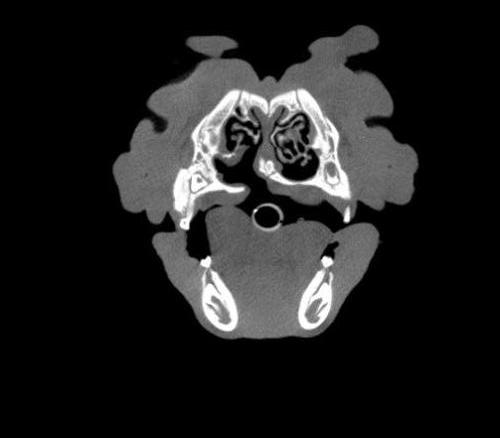

Cone Beam Computed Tomography

The Center now provides advanced imaging via cone beam CT. Cone beam CT is excellent for visualization of bony structures of the skull, nasal cavity, teeth, and ears. Cone beam CT is especially helpful for diagnosing dental disease and evaluation of jaw fractures. It can also be useful for evaluating the sinuses and tympanic bulla. Cone beam CT can be used in conjunction with nasal biopsy and culture to evaluate nasal discharge whether chronic or acute.

Repair of Maxillofacial Fracture

Pets can be involved in trauma that can cause fractures to their head, teeth, and jaw bones. Correctly repairing these fractures is extremely important for your pet to have normal function of their mouth. If a jaw fracture is allowed to heal in an abnormal position, your pet may have great difficulty chewing and can be in significant pain. Many fractures can be successfully treated with minimally invasive oral procedures, but more complicated cases may require bone plating techniques. The Center offers cone beam CT imaging which provides extremely detailed images of the bones of the head and skull. Advanced imaging with CBCT facilitates selection of the best surgical technique to get your pet back to eating and comfort as soon as possible.